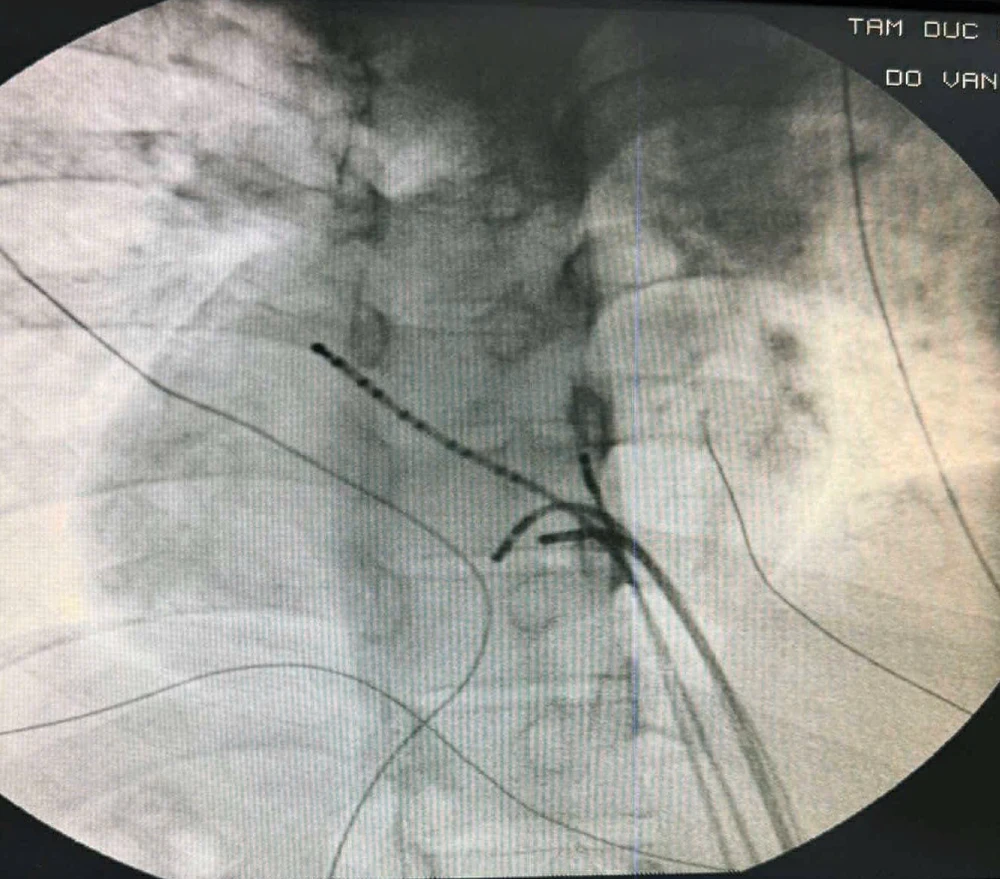

Đây là một trường hợp lâm sàng khá hiếm gặp: bệnh nhân có hội chứng WPW (Wolff-Parkinson-White) do đường dẫn truyền phụ, kết hợp với tình trạng dextrocardia – quả tim nằm bên phải – và các tạng như gan, dạ dày, tĩnh mạch chủ dưới hoán đổi vị trí trái phải hoàn toàn.

Với cấu trúc tim bất thường như vậy, các dụng cụ và phương pháp tiếp cận thông thường có thể sẽ không phù hợp và không thực hiện được cắt đốt đường phụ. Đồng thời, điện tâm đồ bề mặt cũng bị hạn chế trong việc định vị chính xác đường dẫn truyền phụ trong tim.

Sau khi đánh giá cẩn thận cấu trúc tim và xác định chỉ định cắt đốt đường dẫn truyền phụ là cần thiết, đội ngũ bác sĩ tại Bệnh viện Tim Tâm Đức đã quyết định thực hiện thủ thuật thăm dò tiên tiến 3D bằng hệ thống dựng hình 3 chiều carto.

Các catheter xoang vành và các buồng tim được dựng hình lại như hình vẽ, và tiến hành tìm đường dẫn truyền phụ bằng kinh nghiệm suy luận giải phẫu tim và không gian 3D.